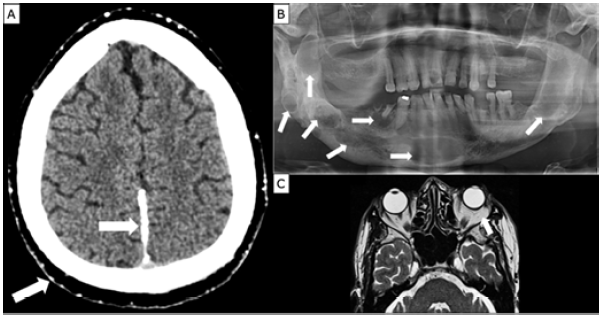

The day after being admitted, i.e., January 25, 2018, multiple imaging studies were ordered. Chest x-ray showed no skeletal malformations; non-contrast brain computed tomography scan revealed multiple calcifications in the scalp, tentorium cerebelli, falx cerebri, and basal ganglia (Figure 4A); orthopantomography showed an extensive lesion at the base of the mandible and multiple circumferential and well-defined radiolucent lesions at the angle and body of the mandible (Figure 4B); gadolinium-enhanced magnetic resonance showed left subconjunctival infraorbital fat involvement associated with focal compromise of the lower posterior sclera of the left eye ball (Figure 4C).

Imaging studies. A) brain computed tomography scan showing calcifications in falx cerebri and tentorium cerebelli; B) orthopantomography indicating multiple lesions in mandibular body and branch; C) gadolinium-enhanced magnetic resonance showing orbits (left subconjunctival infraorbital fat involvement is observed).

Figure 4: Imaging studies. A) brain computed tomography scan showing calcifications in falx cerebri and tentorium cerebelli; B) orthopantomography indicating multiple lesions in mandibular body and branch; C) gadolinium-enhanced magnetic resonance showing orbits (left subconjunctival infraorbital fat involvement is observed).